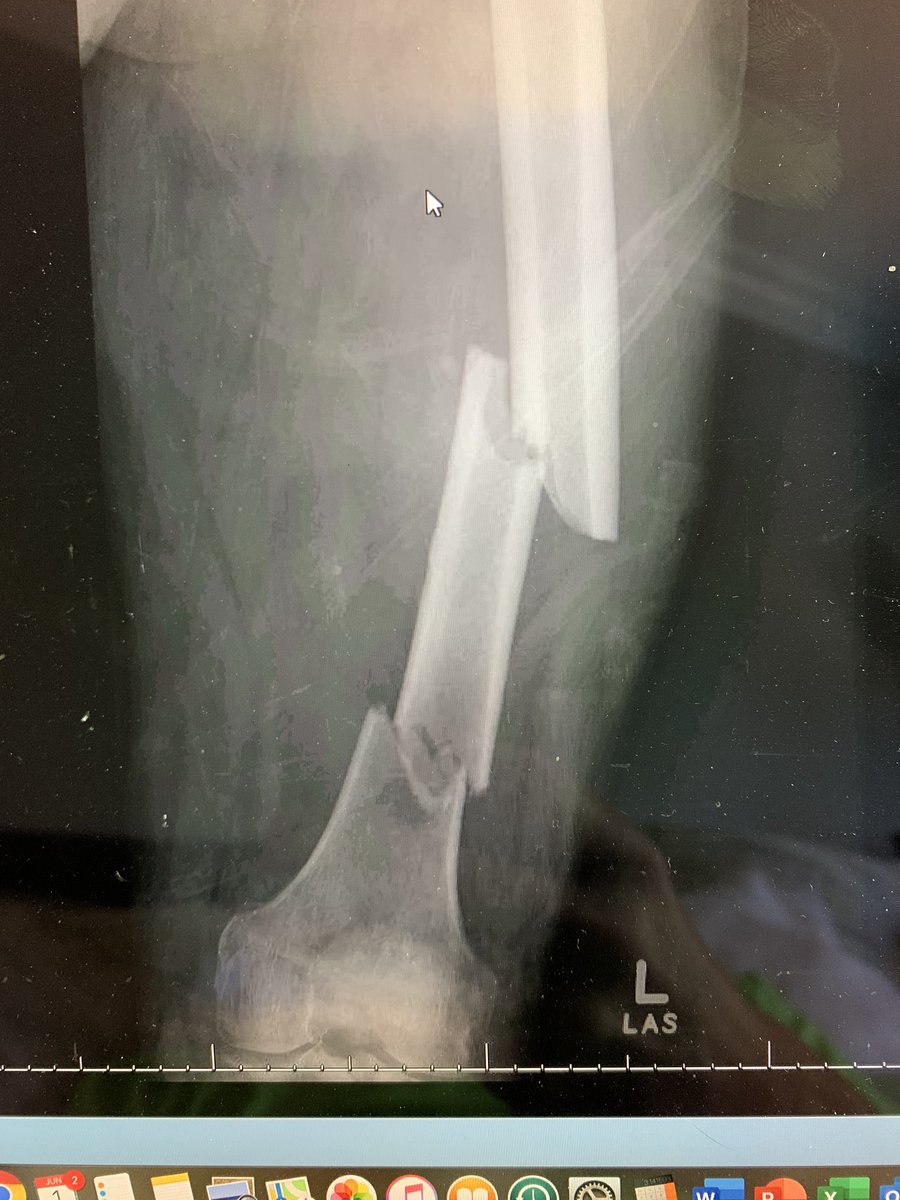

Exchange nailing for management of segmental femur w/ shorter rIMN.

Plate to bridge stress riser.

Discussed full length femur plate, but nail would allow earlier mobilization.